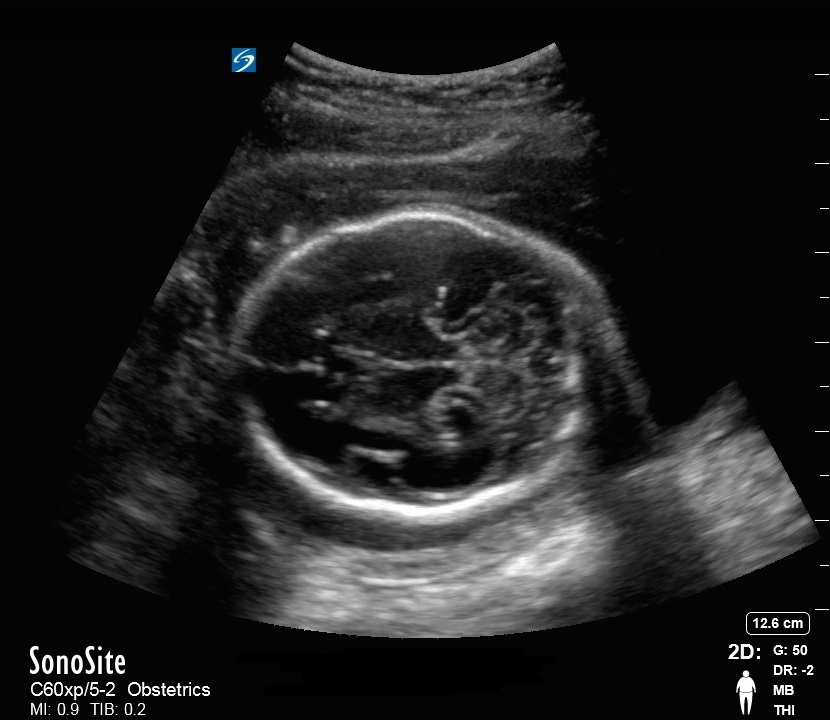

盆腔胎儿头部双顶直径 (BPD) 图像